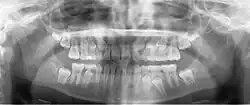

Панорамная рентгенограмма показывает нижние зубы мудрости с горизонтальным ретинированием